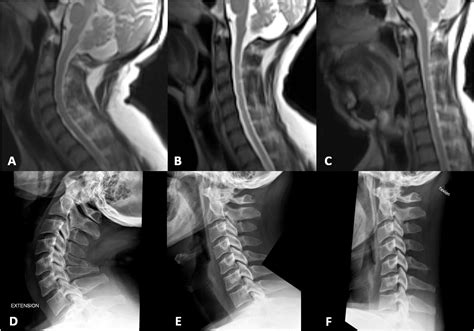

Types of Imaging Modalities Used in Extension

Not all diagnostic tools are designed for dynamic assessment. While standard static MRI is the gold standard for soft tissue detail, specialized versions are required to incorporate movement. Below is a breakdown of the primary technologies utilized for spine extension imaging:

Modality Primary Use Benefit of Extension

Dynamic X-ray (Flexion/Extension) Checking for spinal instability Visualizes vertebral shifting

Upright/Positional MRI Capturing load-bearing pathology Simulates gravity's effect on discs

Dynamic CT Scan High-resolution bony anatomy Identifies subtle fractures or joint impinging

Interpreting Results and Clinical Implications

Once the spine extension imaging is complete, the images are sent to a radiologist. They will compare the neutral images with the extension images, looking for changes in the width of the spinal canal, the position of the vertebrae, and the amount of room available for nerve roots. The clinical significance of these findings must then be correlated with the patient's physical examination. It is entirely possible to have a structural finding on an extension scan that does not explain the patient's symptoms; therefore, the imaging is only one piece of the diagnostic puzzle.